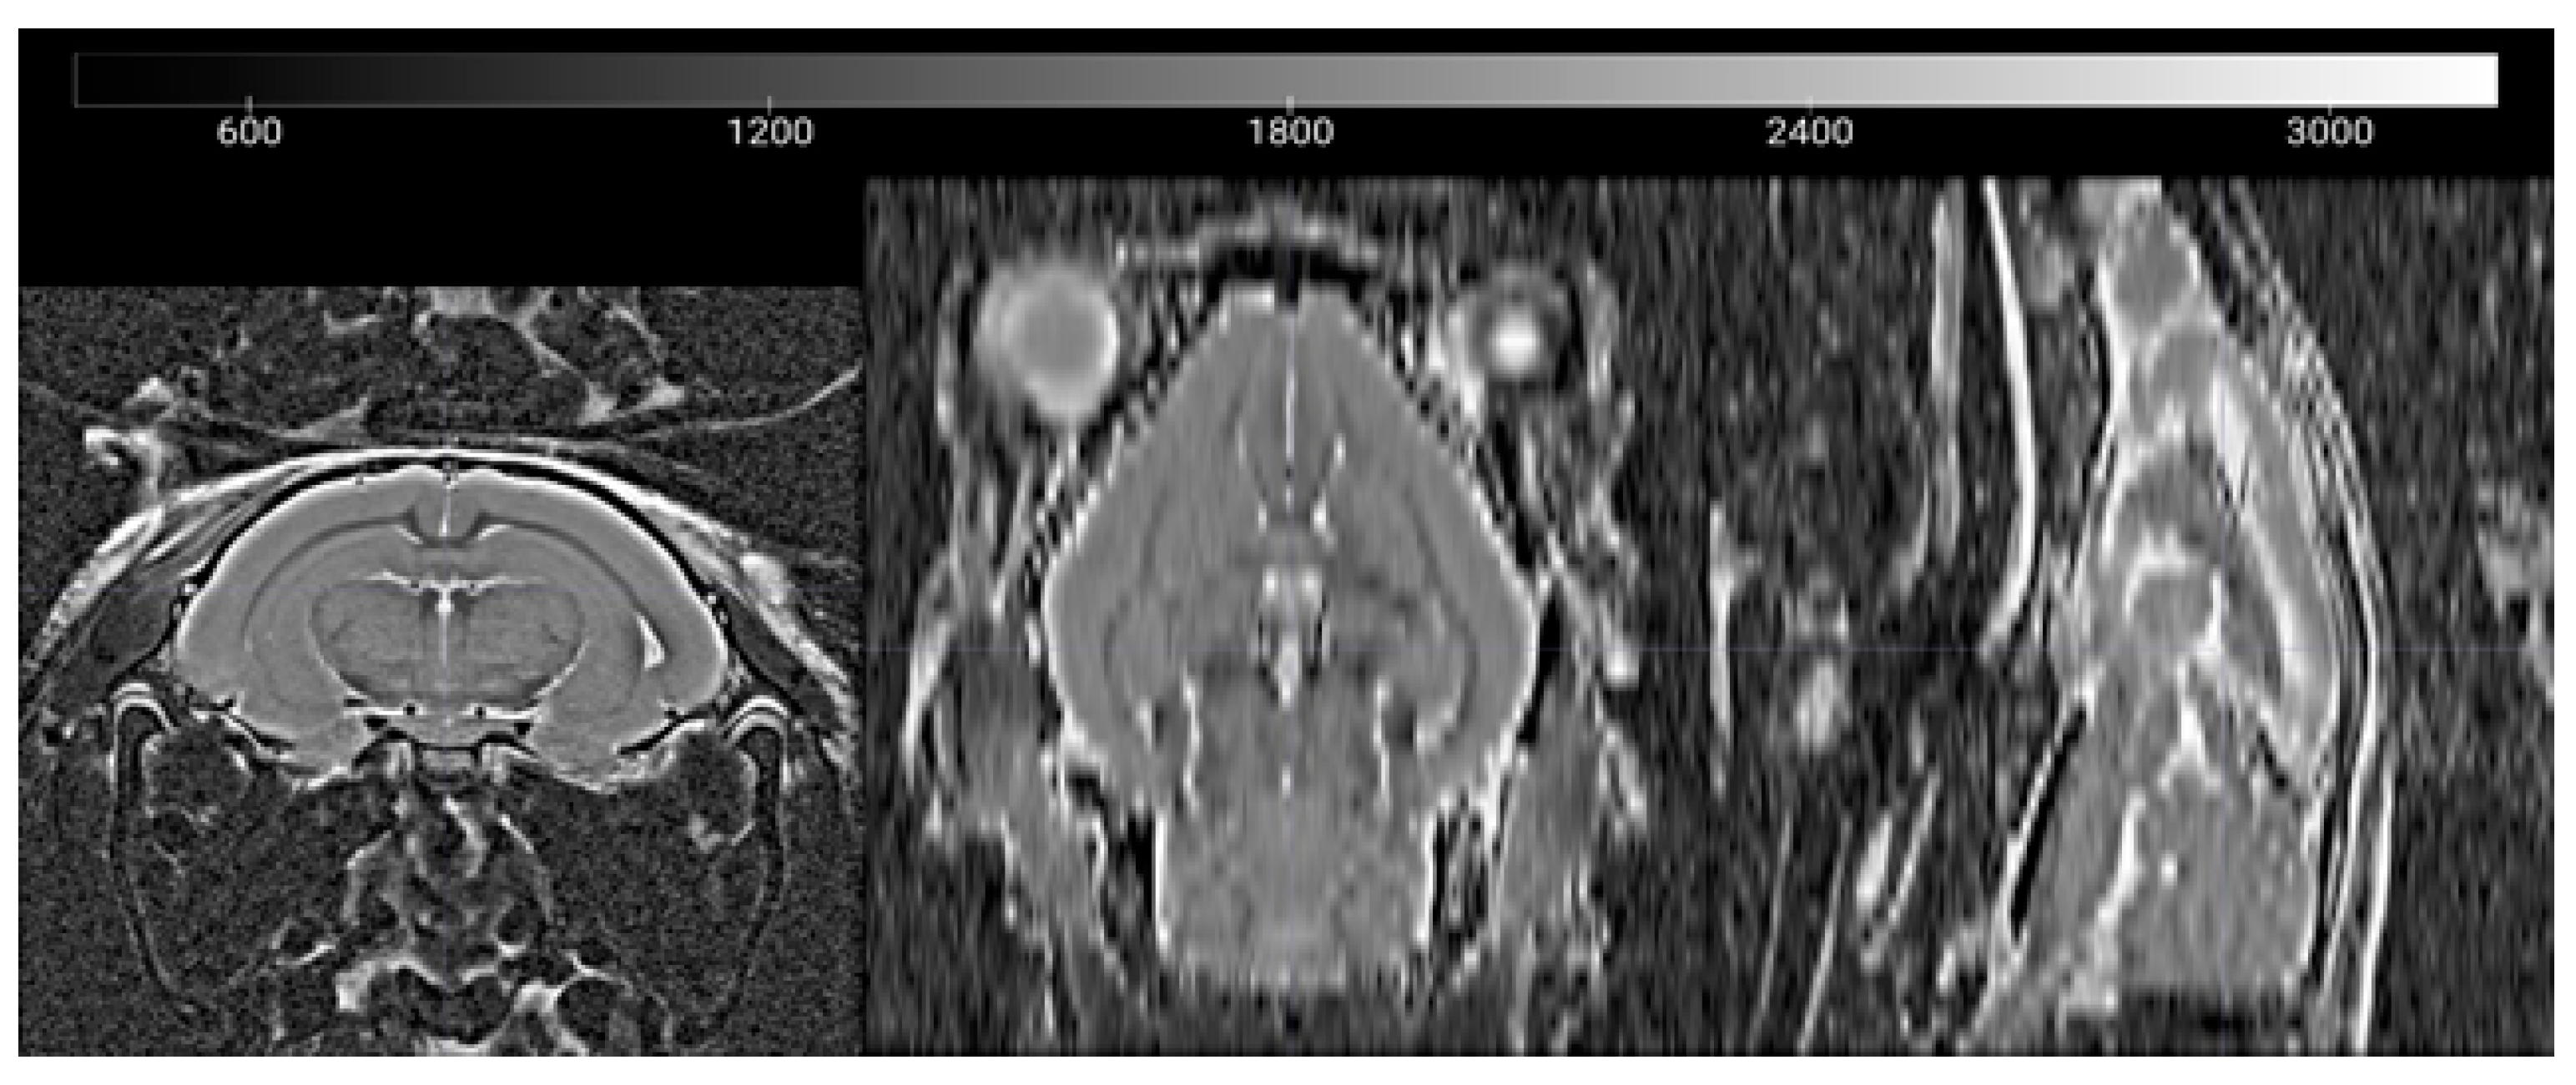

2.2. In Vivo MRI

3.2. Age Dependency of Whole Brain T2, FA, Diffusivity, and Kurtosis Measures